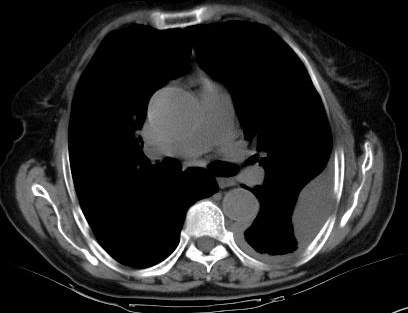

测ct值3-6hu,

既然ct值是3-6hu,还不如考虑包裹性积液。

支持包裹性胸腔积液。

请上传纵隔窗。目前还是支技包裹性积液(明显梭形),即使是间皮瘤并积液也少梭形的。

从图片看,包裹性积液好象更合理,梭形,ct值3-5hu(在哪看到的?);胸膜间皮瘤如此规则,不多见。

左侧背部胸膜肥厚,伴包裹性积液,不考虑间皮瘤.